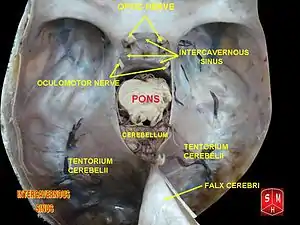

The intercavernous sinuses are two in number, an anterior and a posterior, and connect the two cavernous sinuses[1] across the middle line.

The anterior passes in front of the hypophysis cerebri (pituitary gland), the posterior behind it, and they form with the cavernous sinuses a venous circle (circular sinus) around the hypophysis.